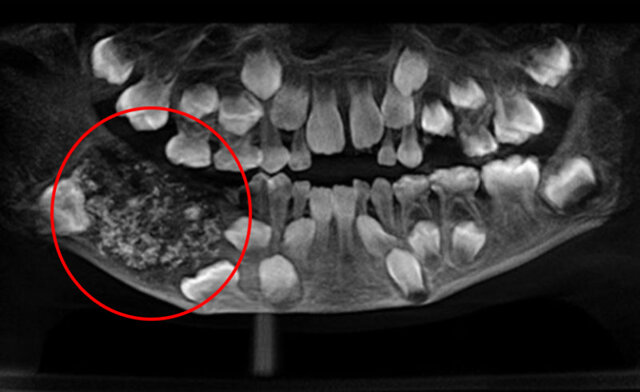

این پسر بچه ۸۰ دندان دارد + عکس

پسربچه ای ۷ ساله که به دلیل دردهای شدید و مکرر به بیمارستان برده شد و بعد از عکسبرداری پزشکان به وجود ۸۰ دندان اضافه در داخل فک او پی برده و بعد از جراحی دندان های اضافه ی او را خارج کردند.

به گزارش اقتصادآنلاین به نقل از برنا؛ پسربچه ای ۷ ساله که به دلیل دردهای شدید و مکرر به بیمارستان برده شد و بعد از عکسبرداری پزشکان به وجود ۸۰ دندان اضافه در داخل فک او پی برده و بعد از جراحی دندان های اضافه ی او را خارج کردند.

اشیک گاوای پسر بچه ی ۷ سالهی هندی که ۸۰ دندان اضافه در فکش داشت بعد از ۴ ساعت جراحی از شر دندان های اضافه نجات یافت. او به دلیل دردهای شدید و بدون وقفه ی دندانهایش به بیمارستانی در بمبعی مورد عکسبرداری قرار گرفت و مشخص شد که او تعداد زیادی دندان اضافه در فک هایش دارد.